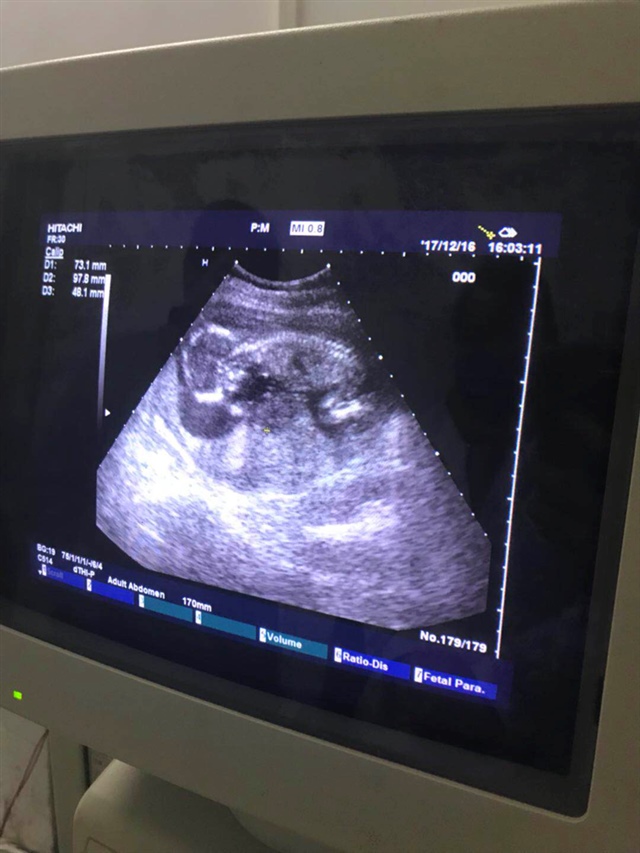

你这张B超是多大的时候照的啊

Ann 🉑82360[帖主]:我是三个半月查的BC

孕囊怎么看呢,求指教

Ann 🉑82360[帖主]:人家说孕囊是长条形是男孩 圆的是女孩,我也不懂

孕囊2.6×3.9×1.5厘米是男女呀